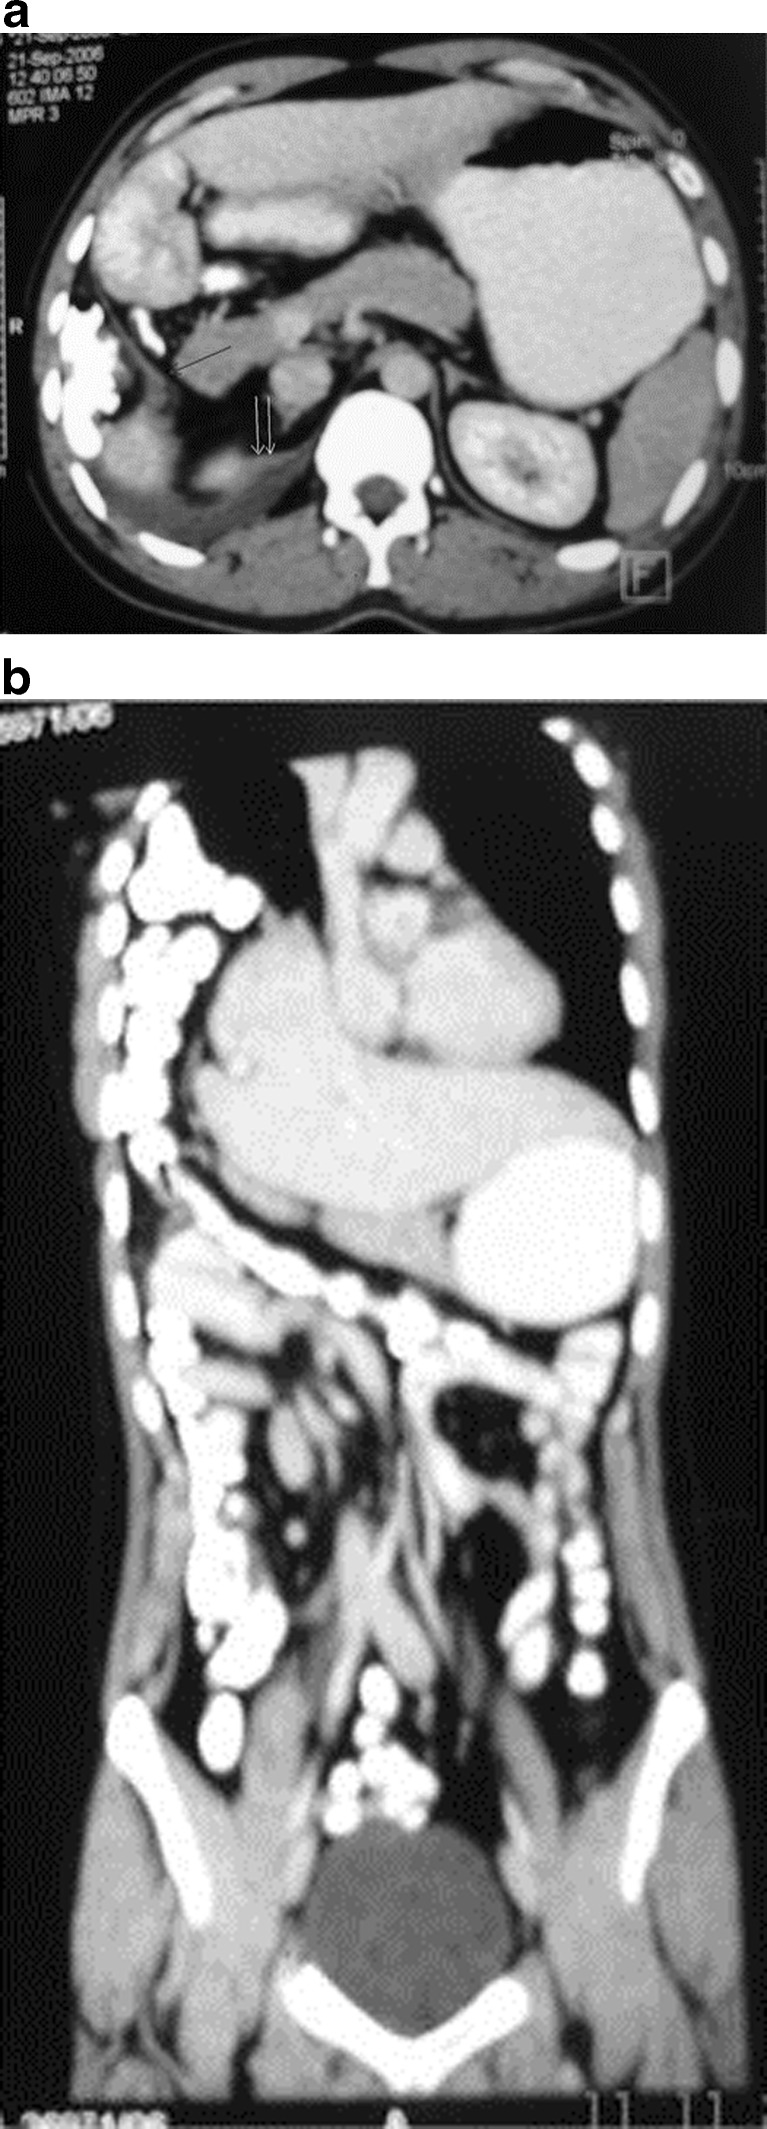

Traumatic Diaphragmatic Hernia

Diaphragmatic rupture can result following major blunt trauma to the lower thorax or abdomen in up to 6% of patients [29, 30]. It is more common on the left side due to an area of congenital posterolateral weakness on the left side and protective effect of the liver on the right hemidiaphragm [31–34]. Helical CT with thinner axial images and higher quality of reformatted images has proven to be more valuable in preoperative detection of traumatic diaphragmatic hernia (Fig. 11).

Fig. 11.

Traumatic diaphragmatic Hernia (a–b) CT scan shows discontinuity in right posterolateral part of diaphragm along with free fluid and herniation of colon into the right chest

CT signs of diaphragmatic injury include direct visualization of injury (free edge of the disrupted diaphragm demarcating the defect is seen), segmental diaphragm non-visualization (low specificity), intrathoracic herniation of viscera, collar sign (focal constriction of the herniated bowel or omentum ) which shows a high specificity of 80.7–100% [31, 32], dependent viscera sign (viscera lies dependent against the posterior chest wall) which shows a specificity of 71–96.5% [32], diaphragm thickening, intramuscular hematoma and peridiaphragmatic active contrast extravasation.

The most commonly herniated viscera is the stomach and colon on the left side and the liver on the right side.